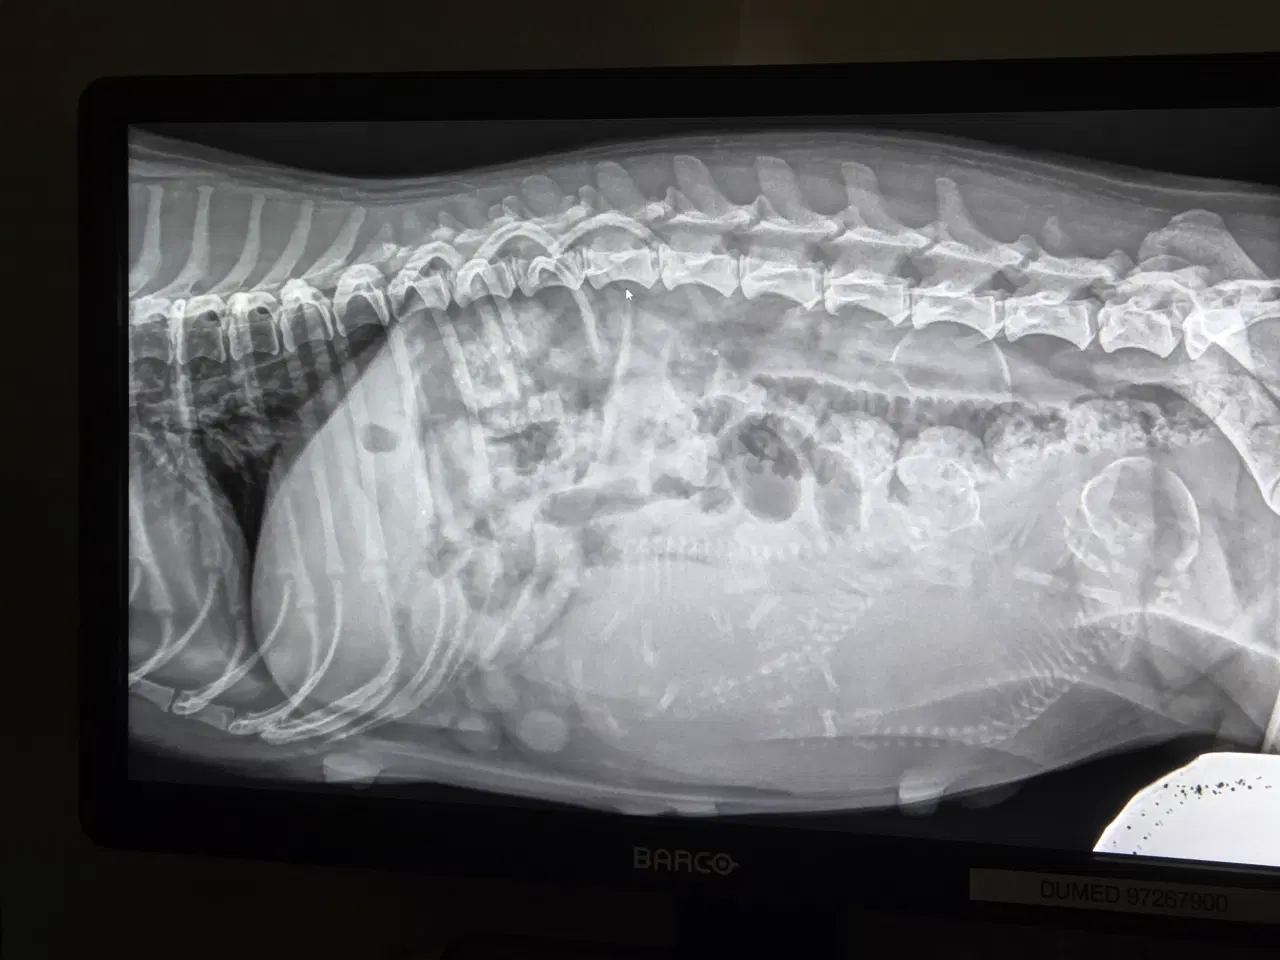

Coton de tulear hvalpe forventes at være salgsklare omkring 1. Juni. Far med flot stamtavle, mor uden. - 2. Gangs forældre. Stueopdræt, hvor der er tid, kærlighed og omsorg højt prioriteret. Følg allerede med i drægtighed og de kommende hvalpe nu (lukket Facebook gruppe) Der følger følgende med til hver hvalp : - tæppe - legetøj - Godbidder - hvalpe halsbånd og Snor - 2 kg foder De vil selvfølgelig være chippet, vaccineret, registreret og fået ormekur x 2 inden de flytter hjemmefra. Ved interesse, kan man sende en sms eller ringe på tlf 41 78 95 60. Reservation når de er født på 1000 kr. Forventes at blive født sidst i påsken 🐶 3 hvalpe udfra røntgen.